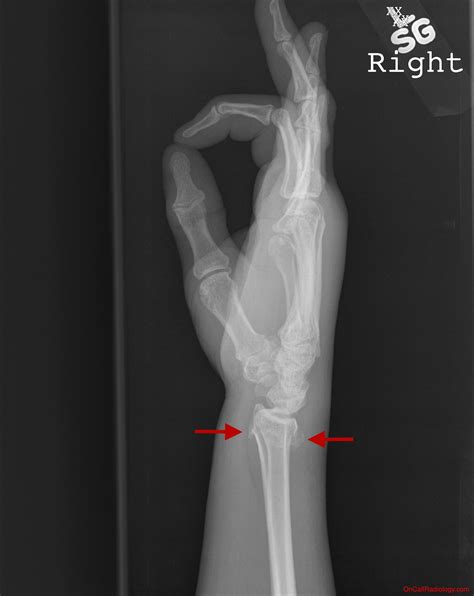

Diagnosing an Ulnar Styloid Fracture

Diagnosing an ulnar styloid fracture typically involves a combination of physical examination and imaging tests. The diagnostic process may include:

• X-rays: These are the primary imaging tool used to confirm the diagnosis. X-rays can show the location and extent of the fracture.

The ulna is one of the two long bones in the forearm, the other being the radius. The styloid process is a small, pointed projection at the distal end of the ulna, near the wrist. This structure plays a vital role in the stability of the wrist joint and the attachment of several ligaments. When this process fractures, it can significantly impact wrist function and cause considerable pain.